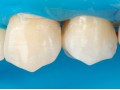

Bezpośrednia licówka kompozytowa w odcinku przednim wykonana…